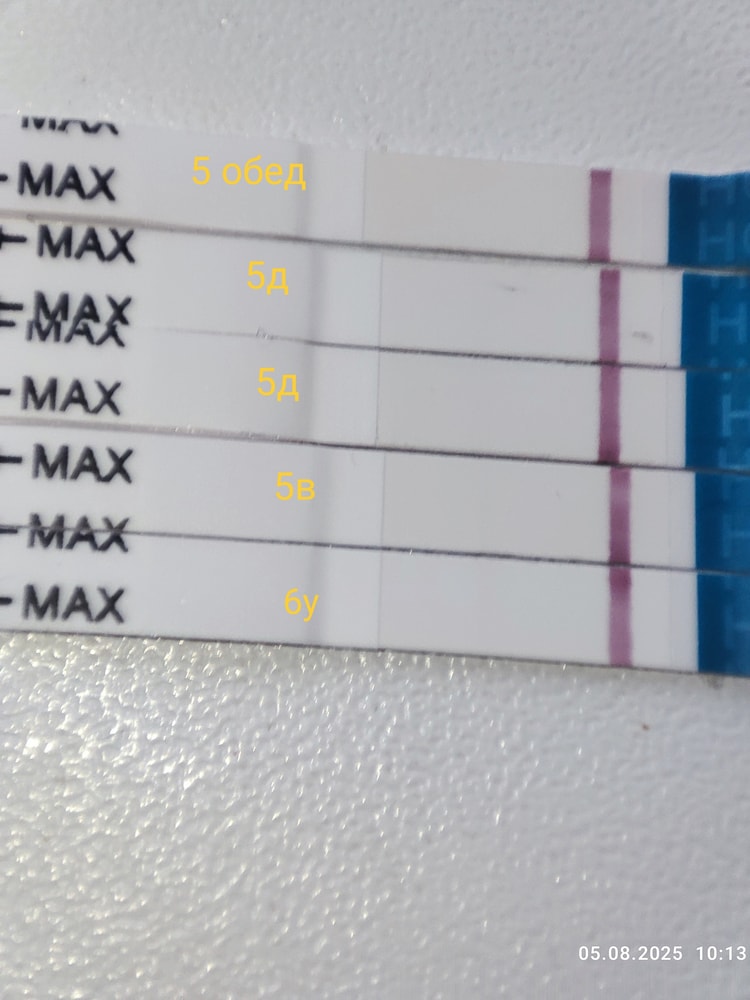

5 дпп 3 бб ЗГТ

Девочки у кого цепляет глаз?

Первые два мама чек

Третий эвик